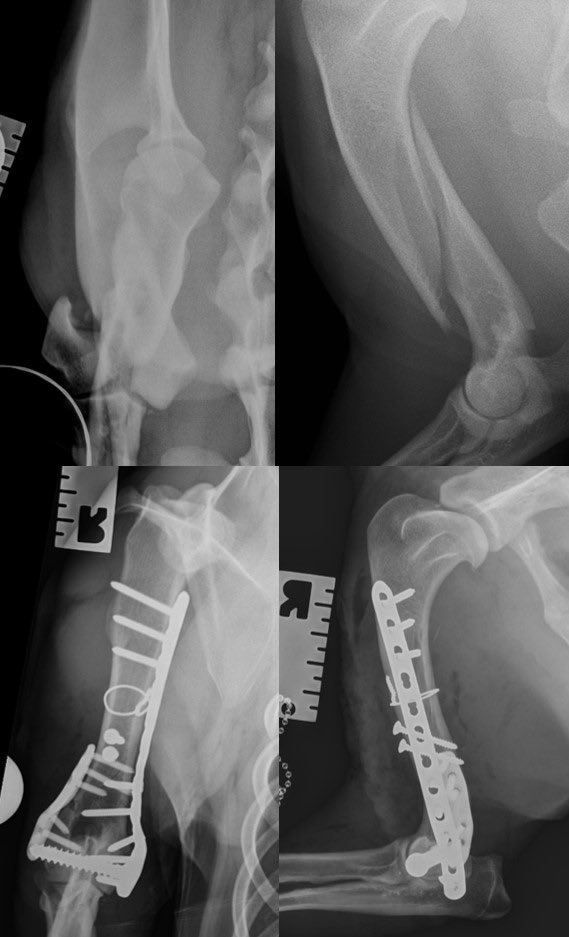

Meet Mac and his unusual, spiral dicondylar fracture. Kept me and the fantastic @CGVetSpecialist team busy today. Thank heavens for the @FusionImplants LEAP to save a bit of time@near the end.

The Lateral Epicondylar Anatomical Plate from @FusionImplants is a great LEAP forwards. It makes repairing these fractures super-satisfying and provides a reliable locking plate construct for these dogs.